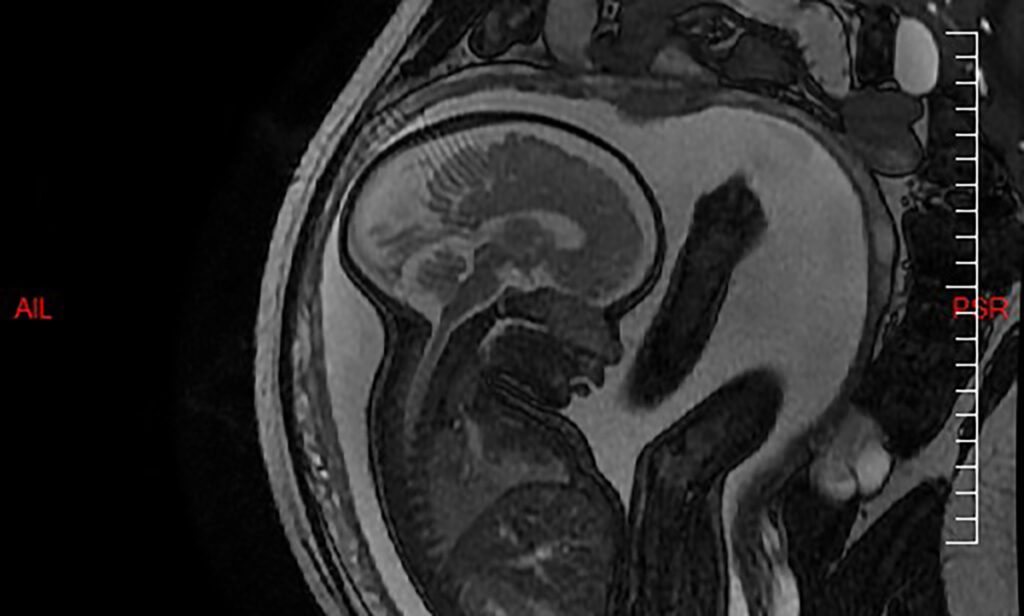

Contrairement au scanner et aux radiographies, l'imagerie par résonance magnétique (IRM) est un examen qui n'utilise pas les rayons X, mais des champs électro-magnétiques Découvrez si l'IRM est sans risque pour le bébé lors de la grossesse Informez-vous sur les protocoles de sécurité et les recommandations médicales concernant l'imagerie par résonance magnétique pour les femmes enceintes

Ces images IRM de bébés dans l’utérus terrifient les internautes ipnoze. Association between MRI exposure during pregnancy and fetal and childhood outcomes L'imagerie par résonance magnétique (IRM) pendant le premier trimestre de grossesse soulève des questions importantes

MRI scan reveals pregnant woman's baby is the True King of the Walls titanfolk. Informez-vous sur les protocoles de sécurité et les recommandations médicales concernant l'imagerie par résonance magnétique pour les femmes enceintes En cas de pathologie maternelle pendant la grossesse nécessitant un acte de radiologie, une IRM peut être utilisée pour limiter les effets de l'irradiation sur le fœtus